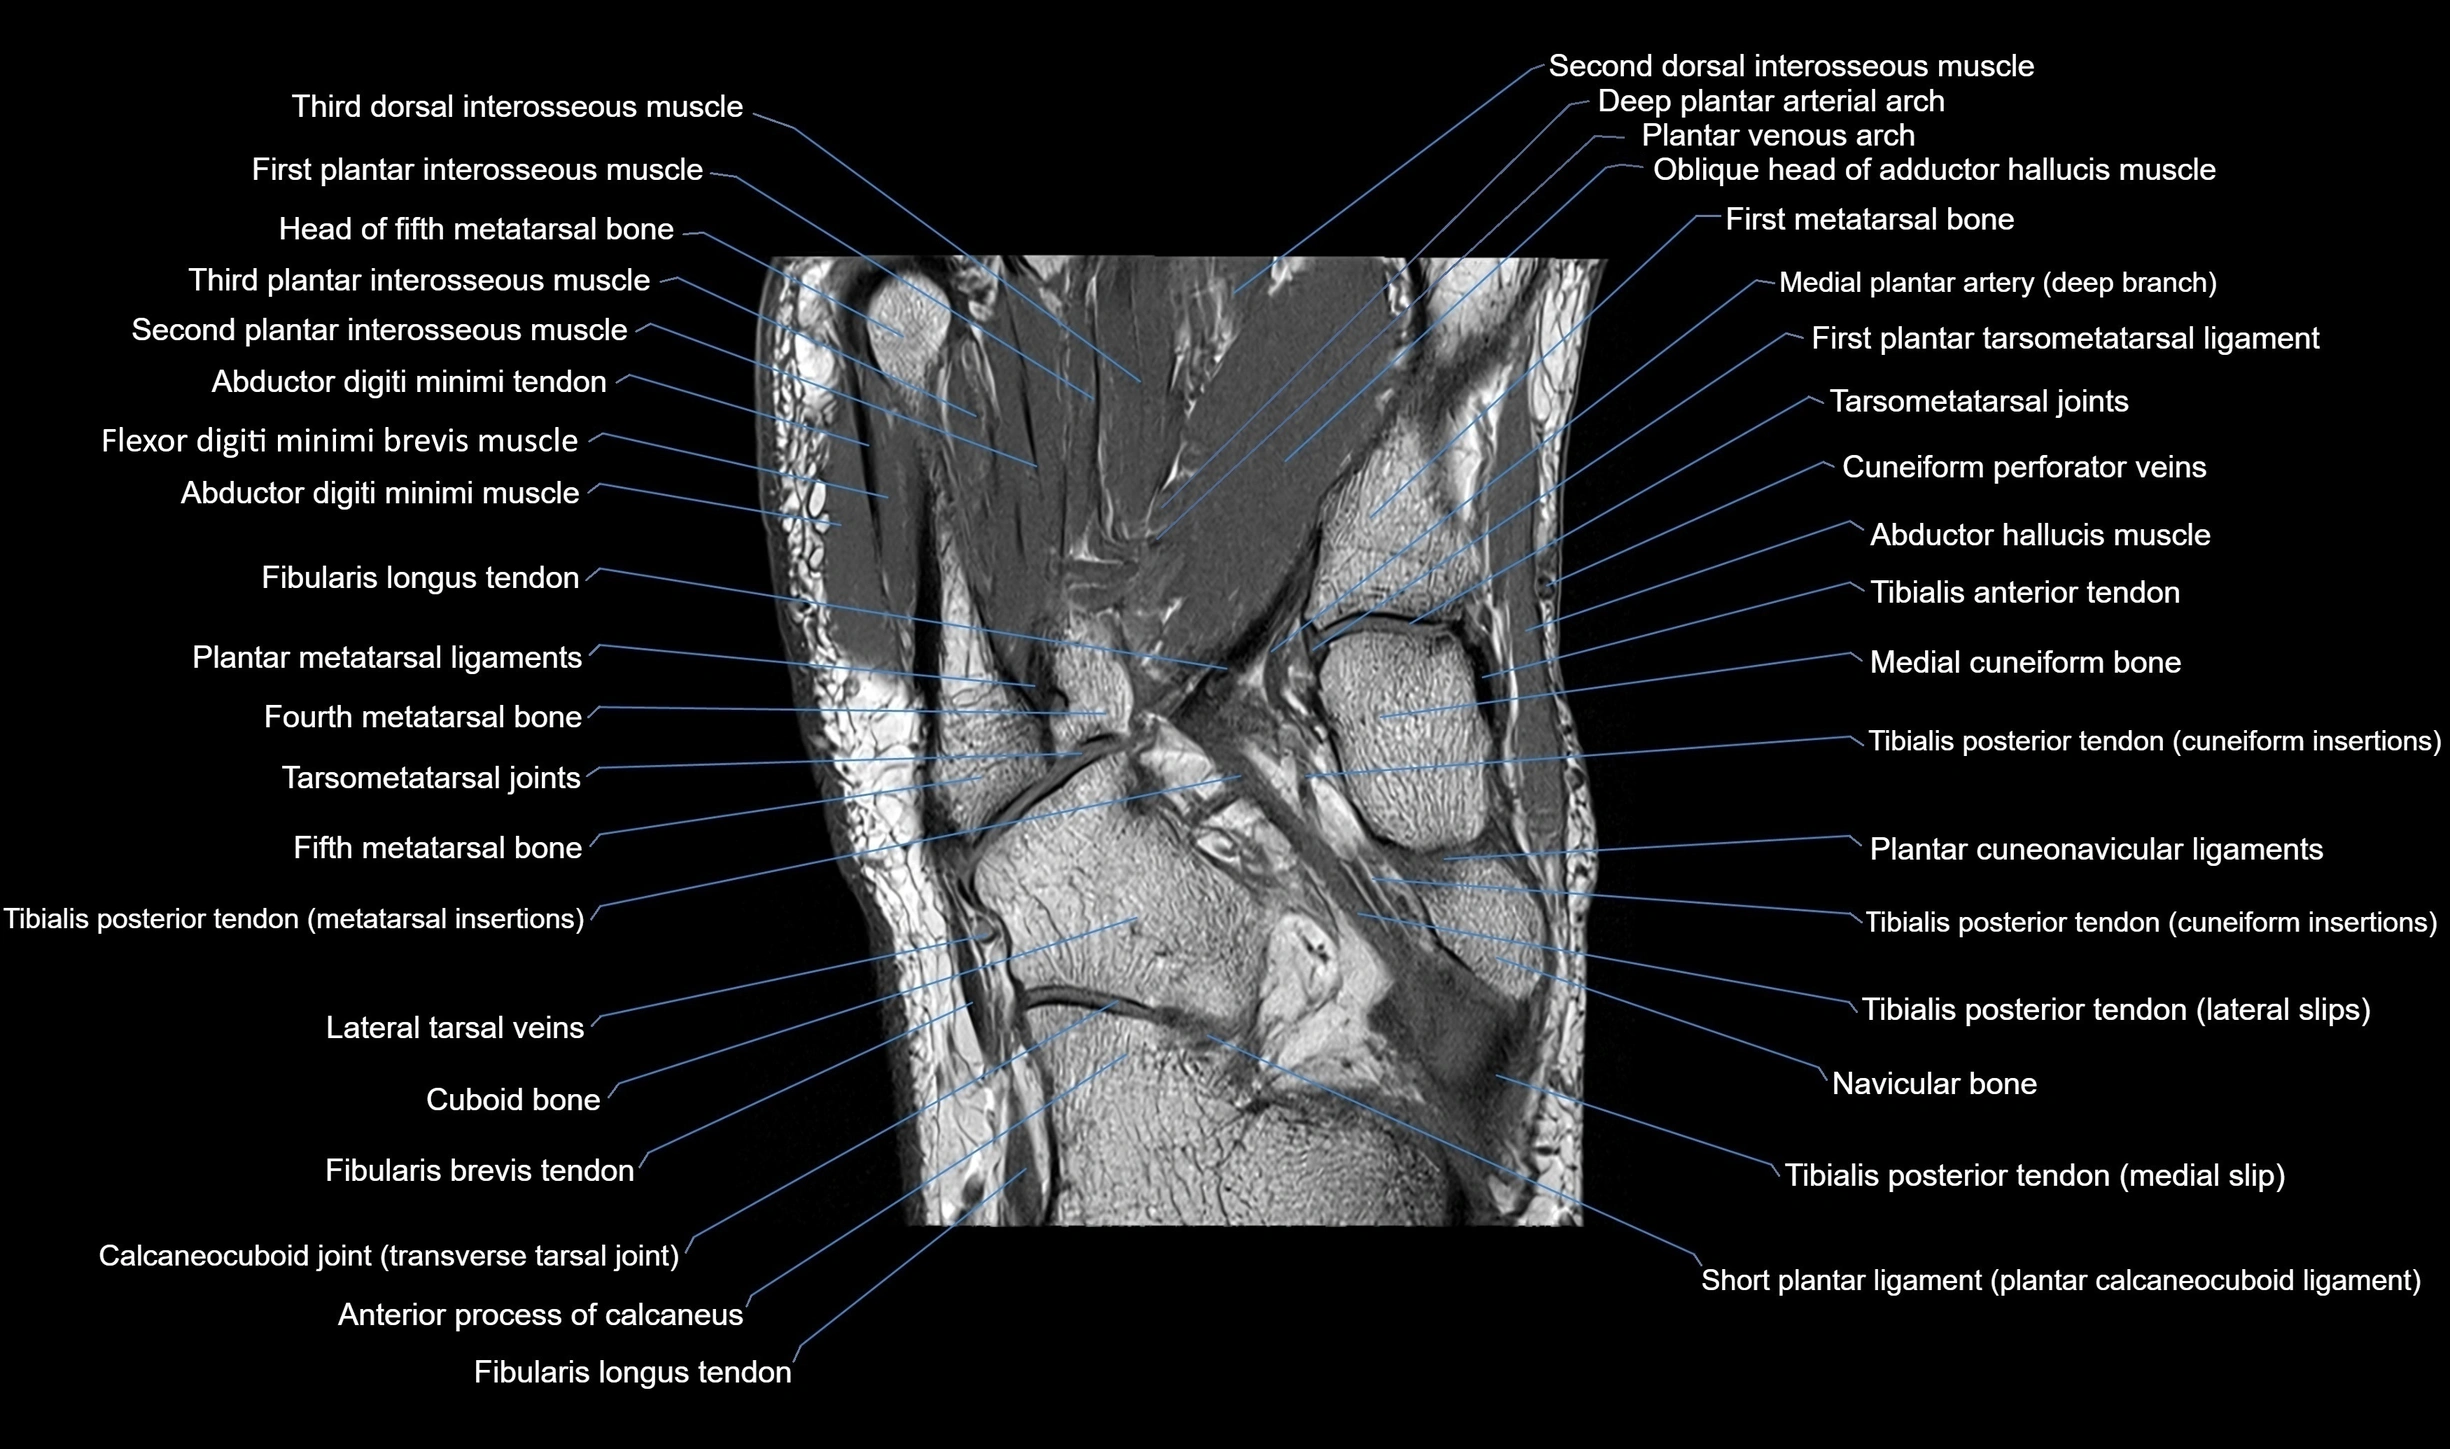

MRI image